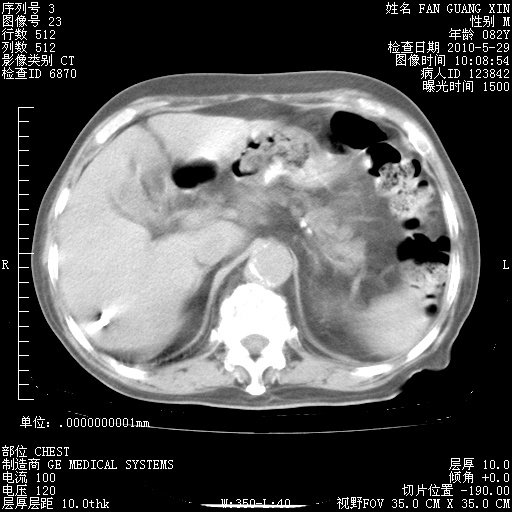

再治疗10天后的肺部CT

阅读此次胸部CT,肺间质渗出性改变较入院时有吸收。目前从体温、白细胞、中性分叶明显增高,肯定存在细菌感染(发生医院感染哦,若无消化道及泌尿系统等感染的依据,肺部感染可能大)。若你院头孢哌酮舒巴坦钠耐药率较高,同意你的方案,若48小时体温仍高,可考虑使用碳青霉稀类抗菌药物,同时可予超声雾化、注意滴数时加大液体量。白蛋白33.30g/L较低哦,需加强营养等支持治疗。